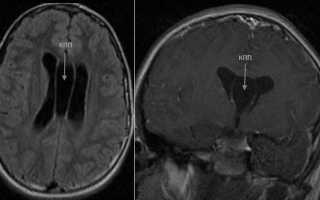

Диагноз кисты полости прозрачной перегородки мозга ставится после проведения МРТ головного мозга и наблюдается примерно у четверти пациентов. Киста может носить как врожденный, так и приобретенный характер.

Для установления диагноза проводят комплекс мероприятий, включающих в себя МРТ, ультразвуковое исследование, а также анализ крови и проверку кровяного давления.

• МРТ – один из самых показательных способов постановки диагноза. При проведении исследования выявляют любые патологические изменения, которые происходят в прозрачной перегородке. Уточняют место локализации кисты, ее диаметр и структуру;МРТ – один из самых показательных способов постановки диагноза.